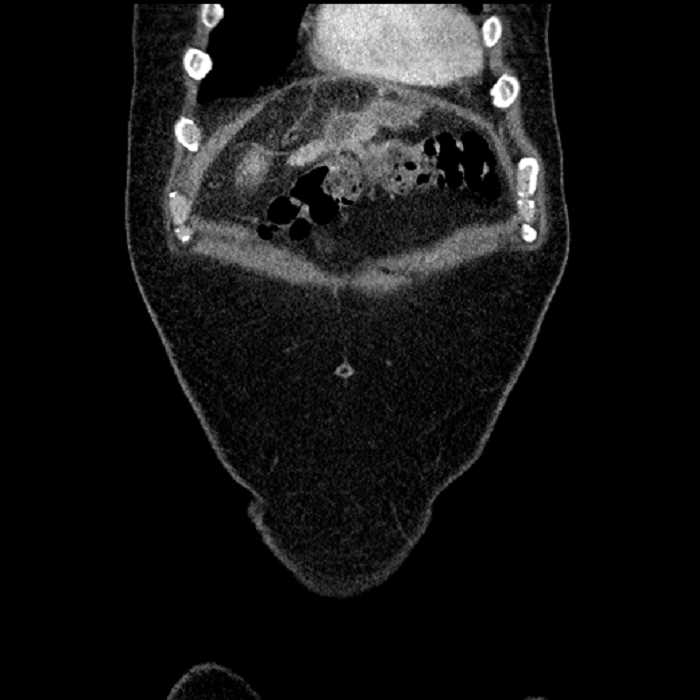

• Large fluid density structure in hepatic segments 7 and 8 measuring 10 x 7 x 7 cm with internal septation and circumferential ill-defined low density compatible with edema

• Peripherally enhancing subcapsular collections along the anterior margin of the left hepatic lobe measuring 3 x 1 cm and 2 x 1 cm

• Clearly marginated fluid density structure in segment 7 and several other scattered tiny hypodensities, which likely represent cysts

• Hepatic abscess

Acute sigmoid diverticulitis complicated by a small contained perforation and a large abscess in the right hepatic lobe. Additional small subcapsular abscesses along the anterior margin of the left hepatic lobe.

• The classic CT imaging appearance is a double target sign with internal low density surrounded by an internal enhancing rim (capsule) and a low density external rim (edema)

Hepatic abscess showing the double target sign with low density internally surrounded by a thin inner enhancing rim (red arrow) and ill-defined outer low density rim (yellow arrow). Blue arrow indicates an internal septation. Red arrows: additional smaller subcapsular abscesses. Red arrow: focal contained perforation associated with diverticulitis.